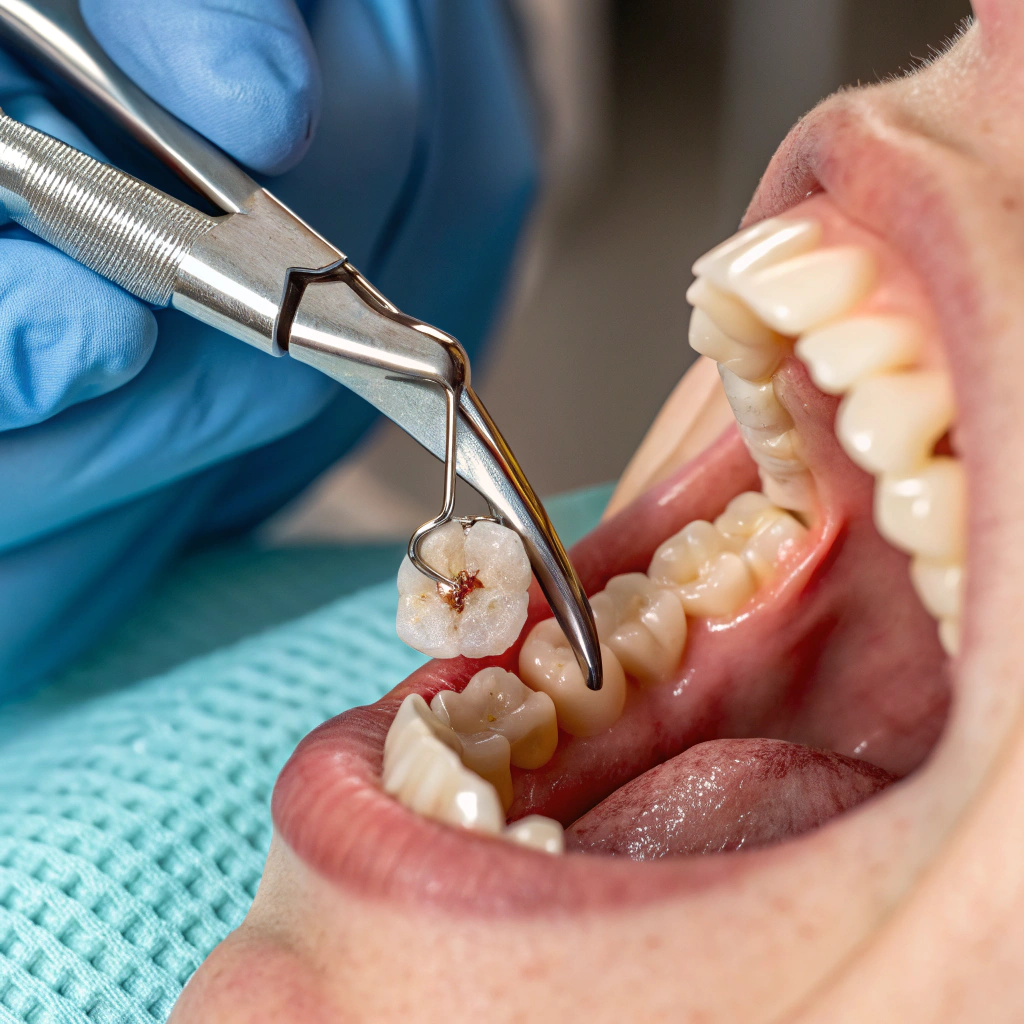

Tooth Extractions

Tooth extractions are performed when a tooth is too damaged, decayed, or impacted to be saved. At Tafodent, we ensure safe, comfortable removal of teeth with a focus on minimizing pain, preserving surrounding structures, and supporting long-term oral health.

- Simple and surgical extractions based on individual need

- Use of local anesthesia or sedation for patient comfort

- Careful removal to protect nearby teeth and bone

- Post-extraction instructions for smooth healing

- Options for tooth replacement, including implants or bridges